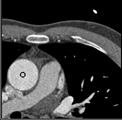

Samples for ascending aorta detection (black circle):

Cluster of candidate points in the ascending aorta.